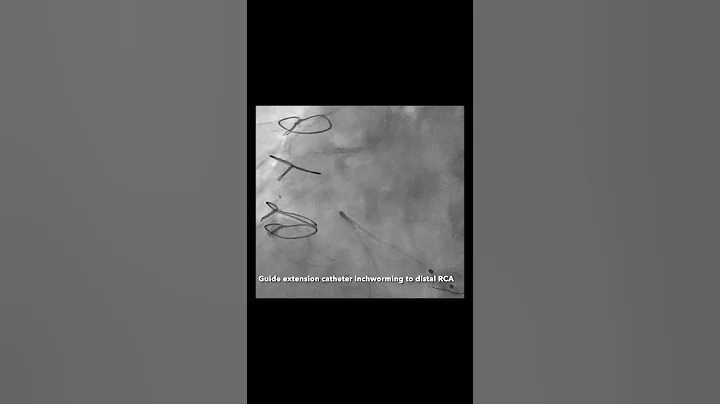

Complex Pci Of Tortuous Calcified Rca Using Rotational Atherectomy With Guide Extension Catheter

43-year-old morbidly obese male with ESRD on HD presented with new onset Class IV angina and NSTEMI (pTnI 2:1U).